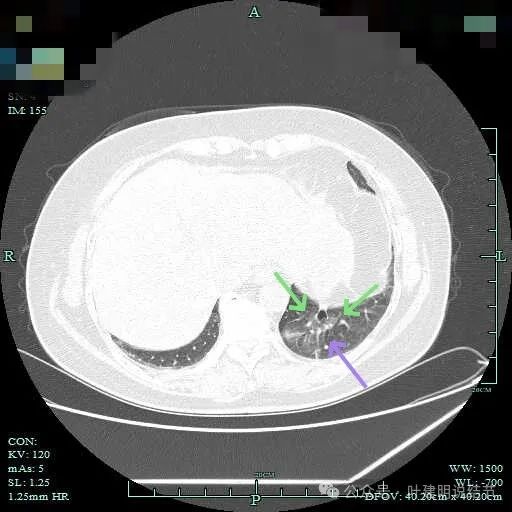

病灶轮廓欠清,较为散在,缺乏聚拢性,似乎有些像斑点状。

有少许磨玻璃成分出现,较前面层面整体轮廓显得清楚点。

到这层面,聚拢性较前明显,密度显杂乱。

磨玻璃成分更明显,实性成分也明显,实性部分收缩力不强,表面不平整,感觉边缘毛糙。

表面浅分叶,磨玻璃成分明显,实性部分密度较高。

表面不平,磨玻璃部分的轮廓与边界清,实性部分占比不小,缺乏收缩力,像是腺泡型。

实性成分占比较高,边上有明显磨玻璃成分,说明含贴亚型。

灶内有小空泡征,磨玻璃部分轮廓与边界清,实性部分虽明显但毛刺征或收缩力等均不明显。

磨玻璃成分以及灶内空泡征。

灶内细支气管扩张明显,实性成分缺乏收缩力,考虑腺泡亚型。

磨玻璃成分也很明显,考虑含贴壁亚型。

上图大部分是磨玻璃成分,边缘的毛刺征,表面有浅分叶。

上图层面已经基本上磨玻璃密度,轮廓清,灶内有囊腔样灶,表面不平。

边缘略显糊,与膈肌贴着。

远侧端有阻塞性炎症的表现,病灶在些层也是磨玻璃密度。

边缘区域略显轮廓不清。